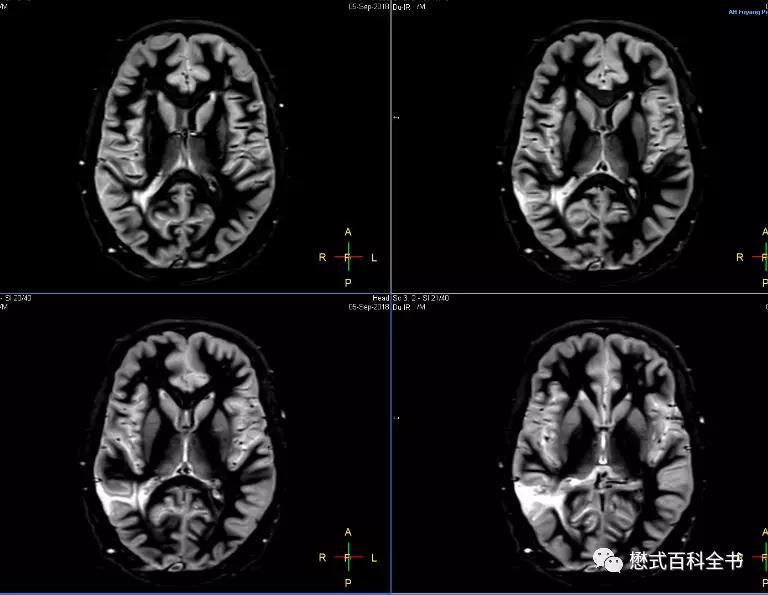

在飞利浦中,原始序列里有专门的脑灰质成像(Grey Matter only)序列和脑白质成像(White Matter only)序列。理论上,1.5T和3.0T由于组织的T1值不同,这个参数有变化,但是我发现,1.5T和3.0T基本上参数设置是一致的。脑灰质成像(Grey Matter only)序列

TR=11000ms或者10500ms,大于10000ms,因为有两个反转;TE=25ms或者20ms;

个人感觉,1.5T效果比3.0T好,可能是1.5T脑组织对比度优于3.0T的原因。